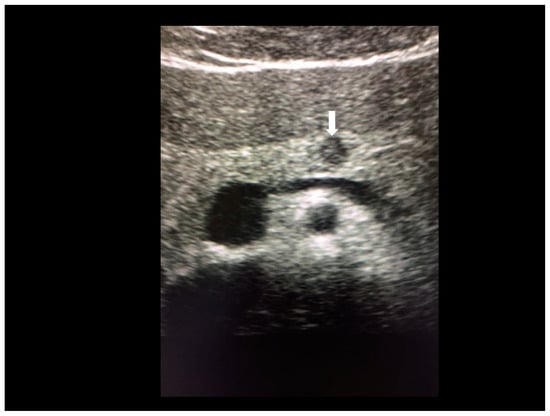

Figure 19. Endometriosis of kidney (see white arrow) confirmed at MRI (A,B).

Endometriosis of kidney is very rare with only ten cases reported in the literature [5,31]. This kind of endometriosis shows a hyperechoic small nodule (Figure 19).